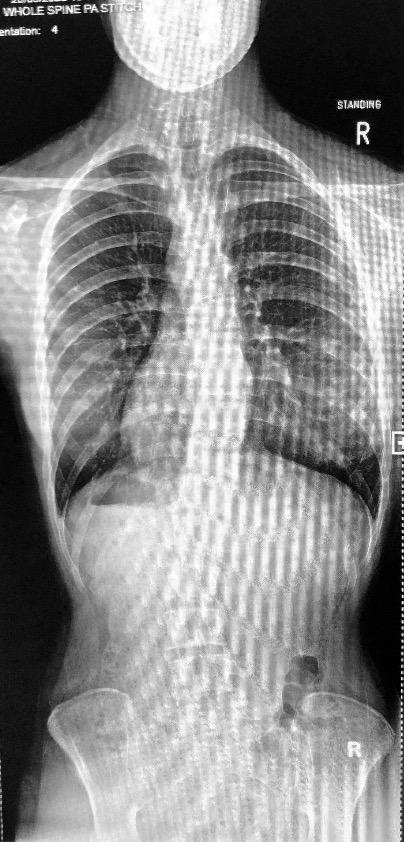

Backtrack is part of the solution to the spinal condition Scoliosis.

If unfamiliar, Scoliosis is the abnormal twisting and lateral curvature of the spine. Scoliosis curves typically progress at a rate of 1 degree a month during the adolescent growth spurt (the fastest rate of progression).

Scoliosis is 3 dimensional ā if one dimension gets worse, the others will follow. The curve progresses in the adolescent stage between 10-16. More commonly with females. 12-16 for males.

Based on extensive research I wanted to design a product which could see what the naked eye could not. To keep an eye on und erlying small changes that would make a long term big impact on the diagnosed. Designing a device which tracks your spinal movements by identifying your muscles reaction.

There are 3 pinnacle points of the spine; the Cervical spine (top) ; Thoracic spine (middle) and Lumbar (bottom). BACKTRACK will consist of 3 individual detectors.